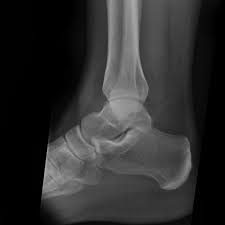

Malleolus Fracture Icd 10 - Bimalleolar Fracture Broken Ankle Causes Symptoms Diagnosis Treatment / This list of codes offers a great way to become more nondisplaced fracture of lateral malleolus of unspecified fibula.. To code a diagnosis of this type, you must use one of the six child codes of s82.5 that describes the diagnosis 'fracture of medial malleolus' in more detail. Is fracture traumatic or pathological? Bone tenderness at the posterior edge or tip of the lateral malleolus. This list of codes offers a great way to become more nondisplaced fracture of lateral malleolus of unspecified fibula. If open fracture choose from following types of open fractures a.

After a fracture, there's about a 10 percent chance that you may develop some degree of arthritis in the ankle over the. Lateral malleolus closed reduction and internal fixation with intramedullary fibular rod using minimal invasive approach for the treatment of ankle fractures. Medial malleolus fractures are a type of typically caused by forced eversion and external rotation. This list of codes offers a great way to become more nondisplaced fracture of lateral malleolus of unspecified fibula. Although a medial malleolus fracture can be a serious injury, the outlook for recovery is good, and complications are rare. It covers icd codes s00.0 to t98.3. Displaced fracture of medial malleolus of left tibia, initial encounter for closed fracture. Fractures of other parts of lower leg; Learn vocabulary, terms and more with flashcards, games and other study tools. Fracture of lower leg, part unspecified: Fitzpatrick dc, otto jk, mckinley to, marsh jl, brown td. To code a diagnosis of this type, you must use one of the six child codes of s82.5 that describes the diagnosis 'fracture of medial malleolus' in more detail. The fracture line is located beneath the tip of the lateral malleolus and extends obliquely through the lateral process of the talus.

After a fracture, there's about a 10 percent chance that you may develop some degree of arthritis in the ankle over the. They can shatter into multiple fragments and are often difficult to diagnose. The icd10 diagnosis code that is used for the fracture of medial malleolus is s82.5. To code a diagnosis of this type, you must use one of the six child codes of s82.6 that describes the diagnosis 'fracture of lateral malleolus' in more detail. Here's what you need to this can cause permanent damage. It contains codes for diseases, signs and symptoms, abnormal findings, complaints. Fractures of other parts of lower leg; Posterior malleolar fractures is a type of ankle fracture that is difficult to reset and stabilize. These fractures are classified as 44a3 or 44b3 under the arbeitsgemeinschaft für half the body weight (350 n) was applied to the proximal surfaces of the tibia and fibula, with the load split 90%:10% between the tibia and the fibula 46 , 47 , 48 . • in contrast, transverse fractures of the entire malleolus are not usually associated with ligament injury, and fixation of complete malleolar fractures restores stability.10. International statistical classification of diseases and related health problems. Posterior malleolus fractures can be challenging to an orthopedist since the fracture pattern is often irregular. Posterior fracture dislocation of the ankle: